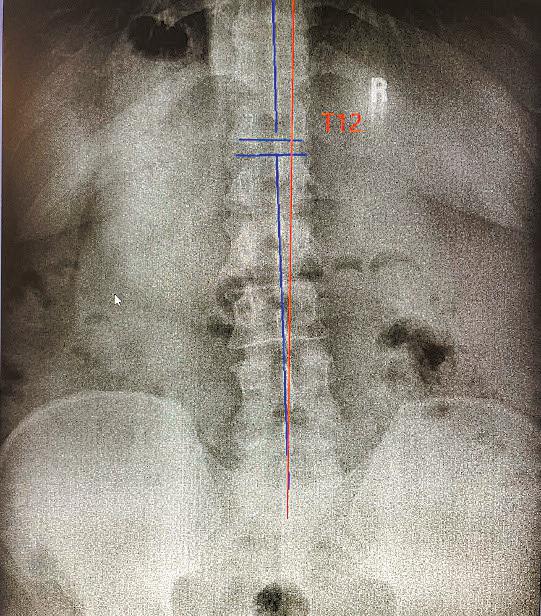

The nervous system controls and coordinates all functions of the body, making its proper functioning essential for overall health. Structural shifts in the spine can obstruct the nerves and interfere with their function. Chiropractors refer to these obstructions as vertebral subluxations, and they are at the core of chiropractic care.

Find out if subluxations are affecting your health with a chiropractic examination with any necessary x-rays for just $59 this month at any Crossroads Chiropractic location.